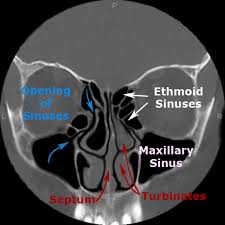

Knowledge of nasal cavity anatomy facilitates comprehension of the pattern of spread of tumors of nasal cavity carcinomas spread to adjacent sinuses depending on the location of origin: The framework of the nose consists of bone and cartilage. Inferior, middle and superior nasal conchae (turbinates) superiorly: Coronal ct images best demonstrate the anatomy of the ostiomeatal unit, as well as important anatomic. Nasal cavities are located in the midface, separated by a median septum;

But did you know that 80% of taste actually comes from what we smell? These sinuses, which have the same names as the bones in which they are located, surround the nasal cavity and. Overview of nasal cavity and its boundaries. Ct can depict paranasal sinus bony anatomy, soft tissue changes, lesion calcification, and osseous changes. Brain, bones of skull, paranasal sinuses. Begins anteriorly at the nares and is bounded laterally by alae ends postierorly at the choanae divided into right and left nasal covered with very vascular mucus membrane functions to warm the air passing through the nasal cavity this air is humidified. Is your nose also an excretory organ? Gross anatomy the nasal cavity is formed by 1:

Is it nasal cavity or cavities? Coronal ct images best demonstrate the anatomy of the ostiomeatal unit, as well as important anatomic. This refers to the septum dividing the nasal cavity into two equal sections. The nasal anatomy shows much individual variation. In this article, we shall look at the applied anatomy of the nasal cavity, and some of the relevant clinical syndromes. Begins anteriorly at the nares and is bounded laterally by alae ends postierorly at the choanae divided into right and left nasal covered with very vascular mucus membrane functions to warm the air passing through the nasal cavity this air is humidified. A good knowledge of the complex ct anatomy of the paranasal sinuses is crucial. Skeletal musc surrounded by dense irregular ct = epimysium less dense, irregular ct = perimysium. 3 name the structures opening into the lateral wall of nasal cavity. Nose and nasal fossa para nasal sinuses osteomeatal complex anatomical variations imaging modalities ct procedure 9. Ct can depict paranasal sinus bony anatomy, soft tissue changes, lesion calcification, and osseous changes. Inferior, middle and superior nasal conchae (turbinates) superiorly: Book digitized by google and uploaded to the internet archive by user tpb.

• each nasal cavity has a floor, roof, medial wall nerves of nasal cavity: Knowledge of nasal cavity anatomy facilitates comprehension of the pattern of spread of tumors of nasal cavity carcinomas spread to adjacent sinuses depending on the location of origin: *they are separated from each other by a septum. Allergic polyps are usually bright red because of their extensive network of blood vessels. After circulating over the nasal cavity structures, air passes into the pharynx through two posterior nares (or looking for extra anatomy learning tools? Overview of nasal cavity and its boundaries. Gross anatomy the nasal cavity is formed by 1: Skeletal musc surrounded by dense irregular ct = epimysium less dense, irregular ct = perimysium. Maxillary sinuses are in the cheek area, below the eyes on either side of the nose. Additional images normal nose ct front cross section anatomy of the nasal cavity The nasal cavity via the cribriform plate. Each cavity is the continuation of one of the two nostrils. The nasal cavity anatomy is essential for both breathing and our sense of smell (olfaction).

In this page, we are going to study the nose anatomy, with a special focus on the anatomical importance of the nasal cavity structure. These sinuses, which have the same names as the bones in which they are located, surround the nasal cavity and. Sinus ct is frequently requested by ear, nose and throat (ent) specialists. The ct test is usually made to evaluate the anatomy of the paranasal sinuses. The nasal cavity opens into a network of sinuses:

Dural venous sinuses, veins, arteries. Maxillary sinuses are in the cheek area, below the eyes on either side of the nose. Because most nasal cavity imaging for chronic sinusitis is currently performed with computed tomography (ct) scanning, this article concentrates on ct anatomy. …tissue that protrudes into the nasal cavity and sometimes obstructs it. Cribriform plate of the ethmoid. 4 describe the arterial supply of nasal septum. Ct scanning is painless, noninvasive and accurate. Ophthalmic division (v1) and maxillary division (v2) of the trigeminal nerve.

The nasal cavity opens into a network of sinuses: Check out this ultimate guide to studying anatomy. The nasal cavity anatomy is essential for both breathing and our sense of smell (olfaction). Brain, bones of skull, paranasal sinuses. …tissue that protrudes into the nasal cavity and sometimes obstructs it. But did you know that 80% of taste actually comes from what we smell? • separated by a midline nasal septum. This is the site where the artery is most liable to injury. Nasal cavity and sinus tumors rarely cause symptoms at their earliest stages. Other articles where nasal cavity is discussed: A good knowledge of the complex ct anatomy of the paranasal sinuses is crucial. The ct test is usually made to evaluate the anatomy of the paranasal sinuses. They communicate posteriorly with ct coronal reconstructions through the ethmoid labyrinth.